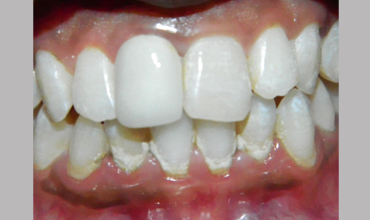

Post Core

Management Of Fractured Tooth With Cast Post & Core